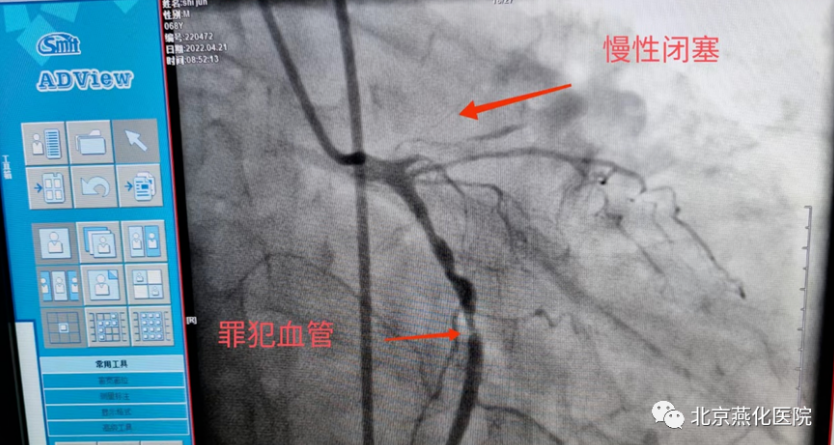

一日凌晨,68岁的石大爷睡眠中突发心前区压榨样疼痛,伴一过性意识丧失,跌倒在地,二便失禁,并胸痛持续不缓解,呼叫120送至我院急诊,心电图提示急性下壁心肌梗死,III度房室传导阻滞,血压74/38mmHg,急诊立即排查新冠肺炎的同时联系我科,秦鹏主治医师立即开通心肌梗死绿色通道,做好防护隔离的同时给予患者静脉溶栓治疗,治疗后患者症状缓解,心电图恢复窦律,抢救成功,后完善冠脉造影提示患者冠脉三支血管病变,右冠状动脉细小,前降支闭塞,回旋支狭窄并可见血栓,李钢主任与患者家属充分交待病情,患者三支血管只剩一支并且是本次心梗的血管,病情危重,需要处理回旋支并尝试开通前降支血管,手术难度及风险较高,患者家属表示理解并要求积极抢救,李刚主任及王志勇、刘丹亮副主任医师给予患者置入IABP(主动脉内球囊反搏)作为保护,反复尝试后给予患者回旋支及前降支闭塞血管进行了治疗,植入冠脉支架,患者转危为安,术后持续IABP辅助,心功能逐渐恢复,抢救成功。